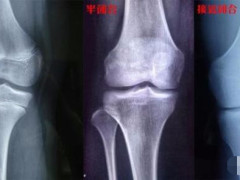

我现在175CM,觉得自己有点矮,现在18岁了,想知道自己还可以长高吗?如果想增高的话需要检查一下骨骺线是否